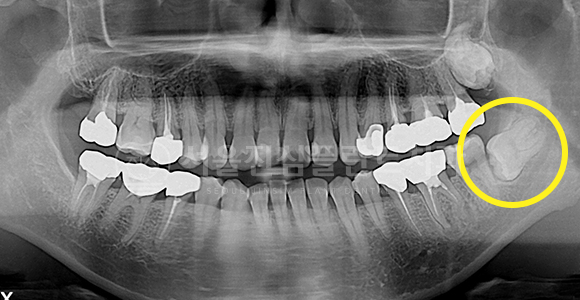

고난이도 매복 사랑니 발치

AFTER

하악 신경관에 근접한 고난이도 사랑니도 안전하게 발치합니다.

멀리 가지 않아도 우리 집 앞에서 대학병원급의 사랑니 발치 진료를 보여드립니다.